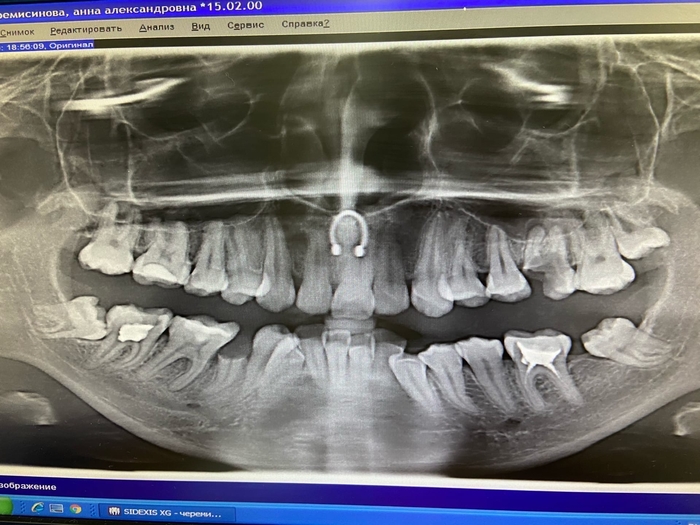

Снимок моих зубов до лечения. Есть несколько осколков, которые образовались из-за того, что я боялась идти к врачам, потому что боялась оскорблений.